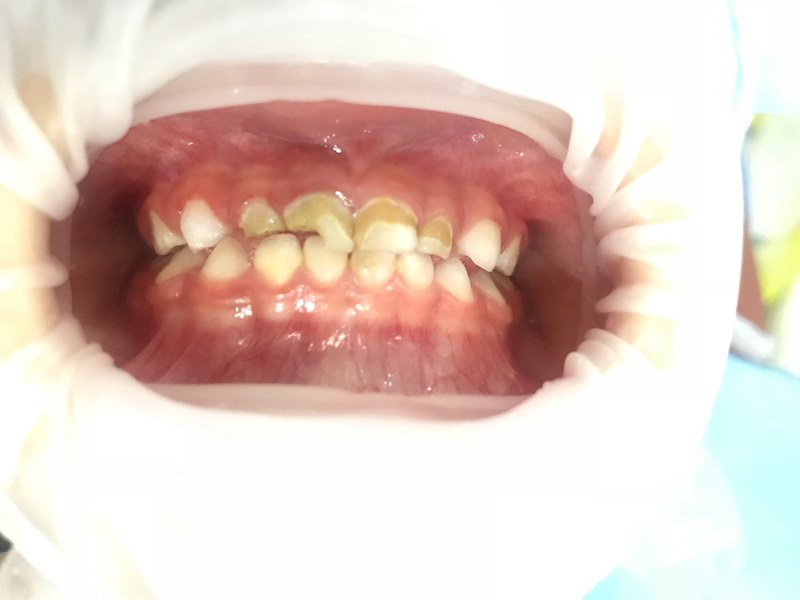

1,重癥低齡兒童齲,不能配合治療者。2,殘障兒童齲,不能配合治療者。 3,患有嚴(yán)重牙科恐懼癥者。 4,牙外傷不能配合治療者。 5,門診不能配合治療,亦不能配合使用笑氣及口服藥物鎮(zhèn)靜的牙病患者。 全麻下一次性牙齒治療前后效果對比

對于年齡很小的小朋友,家長們還要注意一種我們稱之為“喂養(yǎng)齲”也稱“奶瓶齲”的蛀牙。這是低齡兒童齲的一種特殊類型,主要由于不良的喂養(yǎng)習(xí)慣所致,包括:含奶瓶入睡、牙齒萌出后喂夜奶、延長母乳或奶瓶喂養(yǎng)時間、過多飲用含糖飲料等,其在臨床上常表現(xiàn)為下圖的環(huán)狀齲樣子。在寶寶喝完奶后,可以用溫開水給寶寶漱口,能有效清洗、沖走奶液在口腔中的殘渣,保持口腔環(huán)境良好。6個月開始就應(yīng)當(dāng)減少夜奶次數(shù),9個月左右應(yīng)該斷夜奶,讓孩子和大人都能得到很好的休息。